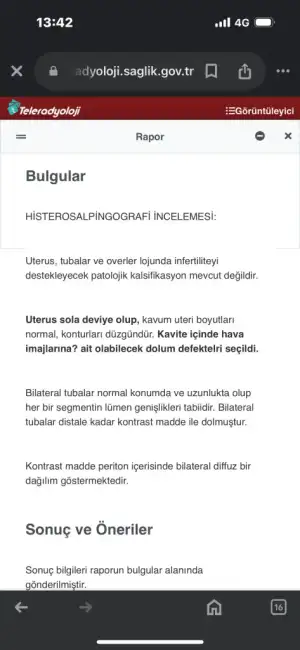

rahim sola eğik dönük demek ama detayını tabi doktor bilirKızlar hsg raporum çıkmış anlayan varsa bakabilirmi

Sonucunu doktoruna ilet wp üzerinden numarasını verdiyse veya hastaneyi ara yönlendirirlerKızlar hsg raporum çıkmış anlayan varsa bakabilirmi